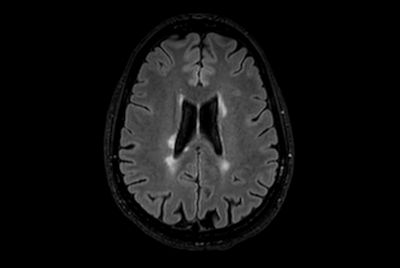

Brain - White matter lesions